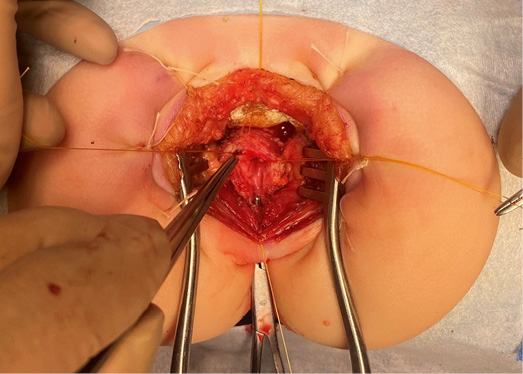

Далее выполнена промежностная проктопластика заднесагиттальным доступом в положении больного на животе. Коротким разрезом до начала наружного сфинктера рассечены ткани и леваторный комплекс. Прямая кишка мобилизована по задней и боковым стенкам на половину окружности кишки. По ходу выделения задней стенки от уровня внутреннего сфинктера и эндоректальной фасции выявлены плотно сросшиеся, с минимальной дифференцировкой тканей, кистозные образования, имеющие как выраженный солидный компонент, так и мелкие кисты с мутным содержимым (взят посев). Имеющие солидный компонент образования расценены как элементы пресакральной кисты и удалены (первое — без вскрытия, второе — с минимальным дефектом, через который выделилось до 10 мл казеозного вещества. Оба образования отправлены на гистологическое обследование). В ходе удаления образований по правому краю последнего позвонка отмечалось капельное выделение ликвора. Наложен Z-образный шов, после чего для герметизации использованы 2 пластины Тахокомб (рис. 4, 5). Интраоперационное наблюдение в динамике — ликвореи нет. Протяженность мобилизации кишки до 8 см.

Рисунки 4, 5.

Заднесагиттальный доступ. Удаление пресакрального образования. Мобилизация прямой кишки

Figures 4, 5.

Posterior horizontal access. Removal of presacral formation. Mobilization of the rectum